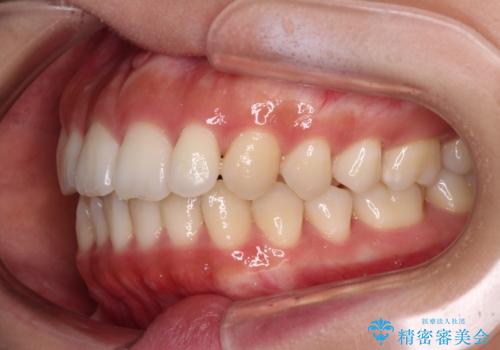

舌の突出癖を改善するためのトレーニングをしっかりと行っていただいたことで、比較的スムーズに治療を進めることができました。

口元の突出感もしっかりと改善することができました。